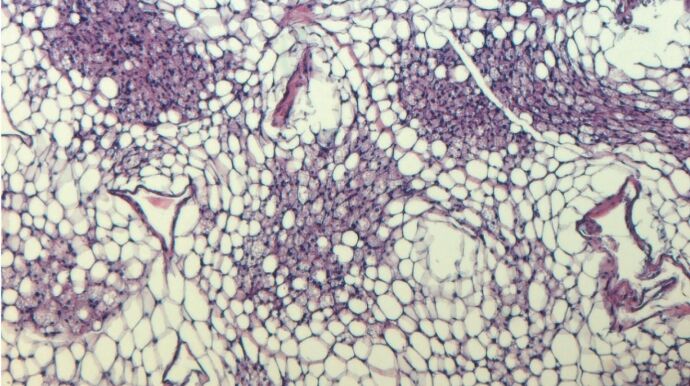

Sin embargo, lo más interesante fue cómo las células de grasa parda intactas respondieron a la llamada de auxilio molecular: Se activaron por la inosina (o simplemente por las células moribundas de su entorno). Así, la inosina avivó el fuego en su interior. Las células de grasa blanca también se convirtieron en sus hermanas marrones. Los ratones alimentados con una dieta alta en energía y tratados al mismo tiempo con inosina se mantuvieron más delgados en comparación con los animales de control y quedaron protegidos de la diabetes.

Los humanos también tienen un transportador de inosina. Entre un dos y un cuatro por ciento de las personas es menos activo debido a una variación genética. "Nuestros colegas de la Universidad de Leipzig han analizado genéticamente a 900 individuos. Los sujetos con el transportador menos activo eran significativamente más delgados de media", explica Pfeifer. Estos resultados sugieren que la inosina también regula la termogénesis en las células de grasa marrón humanas. Por tanto, las sustancias que interfieren en la actividad del transportador podrían ser potencialmente adecuadas para el tratamiento de la obesidad. El fármaco ya aprobado para los trastornos de la coagulación podría servir de punto de partida.

"Sin embargo, se necesitan más estudios en humanos para aclarar el potencial farmacológico de este mecanismo", afirma Pfeifer. Tampoco cree que una píldora por sí sola vaya a ser la solución a la pandemia de obesidad en el mundo. "Pero las terapias disponibles no son lo suficientemente eficaces por el momento. Por tanto, necesitamos desesperadamente medicamentos para normalizar el equilibrio energético en los pacientes obesos", subraya.